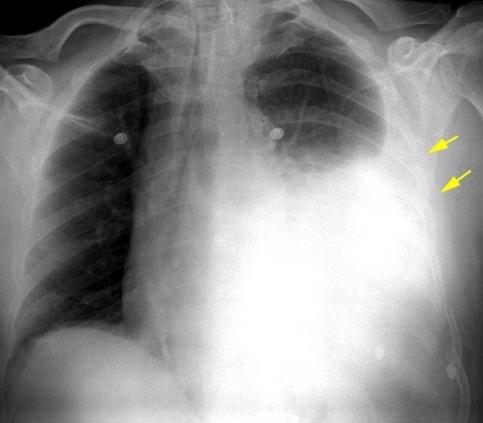

Marzo 2014: Perforación longitudinal distal secundaria a episodio de vómito (síndrome de Boerhaave). Derrame pleural izdo. que evoluciona a empiema.

Wang C-T et al. Tension hydropneumothorax in a Boerhaave syndrome patient: A case report . World J Emerg Med, 2021. Katabathina V et al. Nonvascular, nontraumatic mediastinal emergencies in adults:a comprehensive review of imaging findings. Radiographics. 2011.